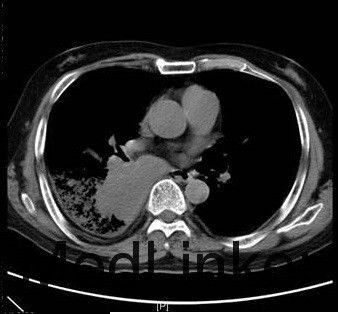

入院情况:入院查体:体温:36.0℃,脉搏:87次/分,呼吸:18次/分,血压:140/78mmHg。发育正常,营养良好,急性面容,表情痛苦,被动体位,神志清楚,精神状态较差,查体合作。呼吸规整,左肺呼吸音粗,右侧中下肺呼吸音减低,左侧肺底未闻及湿性罗音,无胸膜摩擦音。心前区无隆起,心尖搏动未见异常,心浊音界未见异常,心率87次/分,律齐,各瓣膜听诊区未闻及病理性杂音,无心包摩擦音。腹平坦,无腹壁静脉曲张,腹部柔软,无压痛、反跳痛,腹部无包块。肝脏肋下未触及,脾脏肋下未触及,Murphy氏征阴性,肾区无叩击痛,有移动性浊音阳性。 广州医学院一附院:头颅MRI平扫+增强:双侧额叶、半卵圆中心、放射冠多发缺血灶,侧脑室外周脑白质脱髓鞘改变,头颅MRI未见明确转移灶。胸部+上腹部增强CT:右下肺背段肿物,考虑肺癌可能性大,并右肺门淋巴结转移,右下肺阻塞性炎症,肝S5-S7段多发稍低密度结节,考虑转移可能性大。 2015-10-26 血常规乙+CRP:CRP<5.0mg/L;WBC9.910E9/L;NEU8.4810E9/L;LYM0.7510E9/L;NEU%85.6%;LYM%7.6%;RBC3.4910E12/L;HGB115G/L;HCT34.7%;PLT12910E9/L;2015-10-26 血气组合(乳酸):pH7.42;pCO245.5mmHg;pO275mmHg;Na142mmol/L;K3.6mmol/L;Lac5mmol/L;HCO3-(P)29.1mmol/L;ABE4.5mmol/L;sO295%;2015-10-26 凝血四项+血浆D-二聚体(免疫学方法):PT15.48秒;Fib1.27g/L;D-Dimer14500ug/L。2015-10-27 B型钠尿肽前体(PRO-BNP)测定+嘉禾心肌酶组+血清肌钙蛋白Ⅰ(cTnI;免疫学方法):CK-MB5μg/L;cTnI<0.010μg/L;PRO-BNP<70ng/L;AST115U/L;CK344U/L;LDH4583U/L;2015-10-27 凝血四项+血浆D-二聚体(免疫学方法):PT14.66秒;PTA80%;INR1.15;TT17.3秒;APTT33秒;Fib2.12g/L;D-Dimer5670ug/L;2015-10-27 肝功一组:T Bili31.48umol/L;D Bili13.94umol/L;I Bili17.54计算值;T PROT60g/L;ALB36g/L;GLB24.00g/L;ALT74U/L;AST117U/L;ChE3.88KU/L;2015-10-27 血常规乙+CRP:CRP11.16mg/L;hsCRP>5.0mg/L;WBC10.2510E9/L;NEU8.1910E9/L;LYM0.9710E9/L;RBC4.0910E12/L;HGB132G/L;PLT13210E9/L;2015-10-27 血气组合(乳酸):pH7.47;pCO245.8mmHg;pO266mmHg;Na137mmol/L;K3.9mmol/L;Ca1.07mmol/L;Cl93mmol/L;Lac3mmol/L;HCO3-(P)33.1mmol/L;ABE8.5mmol/L;B超:双侧股动脉粥样硬化并多发斑块形成。余双下肢上述动脉、上述静脉未见异常。心内结构未见异常。CDFI心内未见异常血流。左室舒张功能减低。CT:对比2015-10-10CT:1、右肺下叶背段占位,考虑肺癌伴纵隔及右肺门淋巴结转移,病灶较前略增大;2、考虑右肺下叶阻塞性肺炎;3、考虑肺气肿、右侧少量胸腔积液。4、主动脉硬化。5、肝内弥漫斑片状及结节状低密度灶,考虑转移。